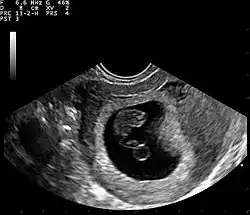

Single intrauterine pregnancy, first trimester. The gestational sac is pictured (black-appearing on ultrasound) containing a fetal pole and yolk sac (circular structure beneath fetal pole.)

Ultrasound

Obstetric ultrasonography may also be used to detect and diagnose pregnancy. It is very common to have a positive at-home urine pregnancy test before an ultrasound. Both abdominal and vaginal ultrasound may be used, but vaginal ultrasound allows for earlier visualization of the pregnancy. With obstetric ultrasonography the gestational sac (intrauterine fluid collection) can be visualized at 4.5 to 5 weeks gestation, the yolk sac at 5 to 6 weeks gestation, and fetal pole at 5.5 to 6 weeks gestation. Ultrasound is used to diagnose multiple gestation, which cannot be diagnosed based on the presence of hCG in urine or blood.[15] Determination of the gestational age of the embryo/fetus is an additional benefit of ultrasound compared to hCG tests.[16]